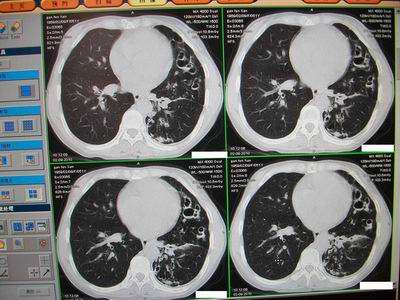

标题: CT24546:支气管扩张?多发性肺囊肿?请高手发表意见吧 [打印本页]

标题: CT24546:支气管扩张?多发性肺囊肿?请高手发表意见吧

临床:女性,51岁,一年来咳嗽、咳痰,反复发作,近两个月带少许血丝。

查体:精神较差,消瘦,余未见明显异常。

图片如下:\

“印戒征”,支扩伴感染

病变主要延肺动脉走形,多发囊状影较小且壁厚,还得先考虑---支扩伴感染。

支扩:腔小、壁厚、多液平;多发性肺囊肿:腔大、壁薄、少液平,本例符合支扩合并感染